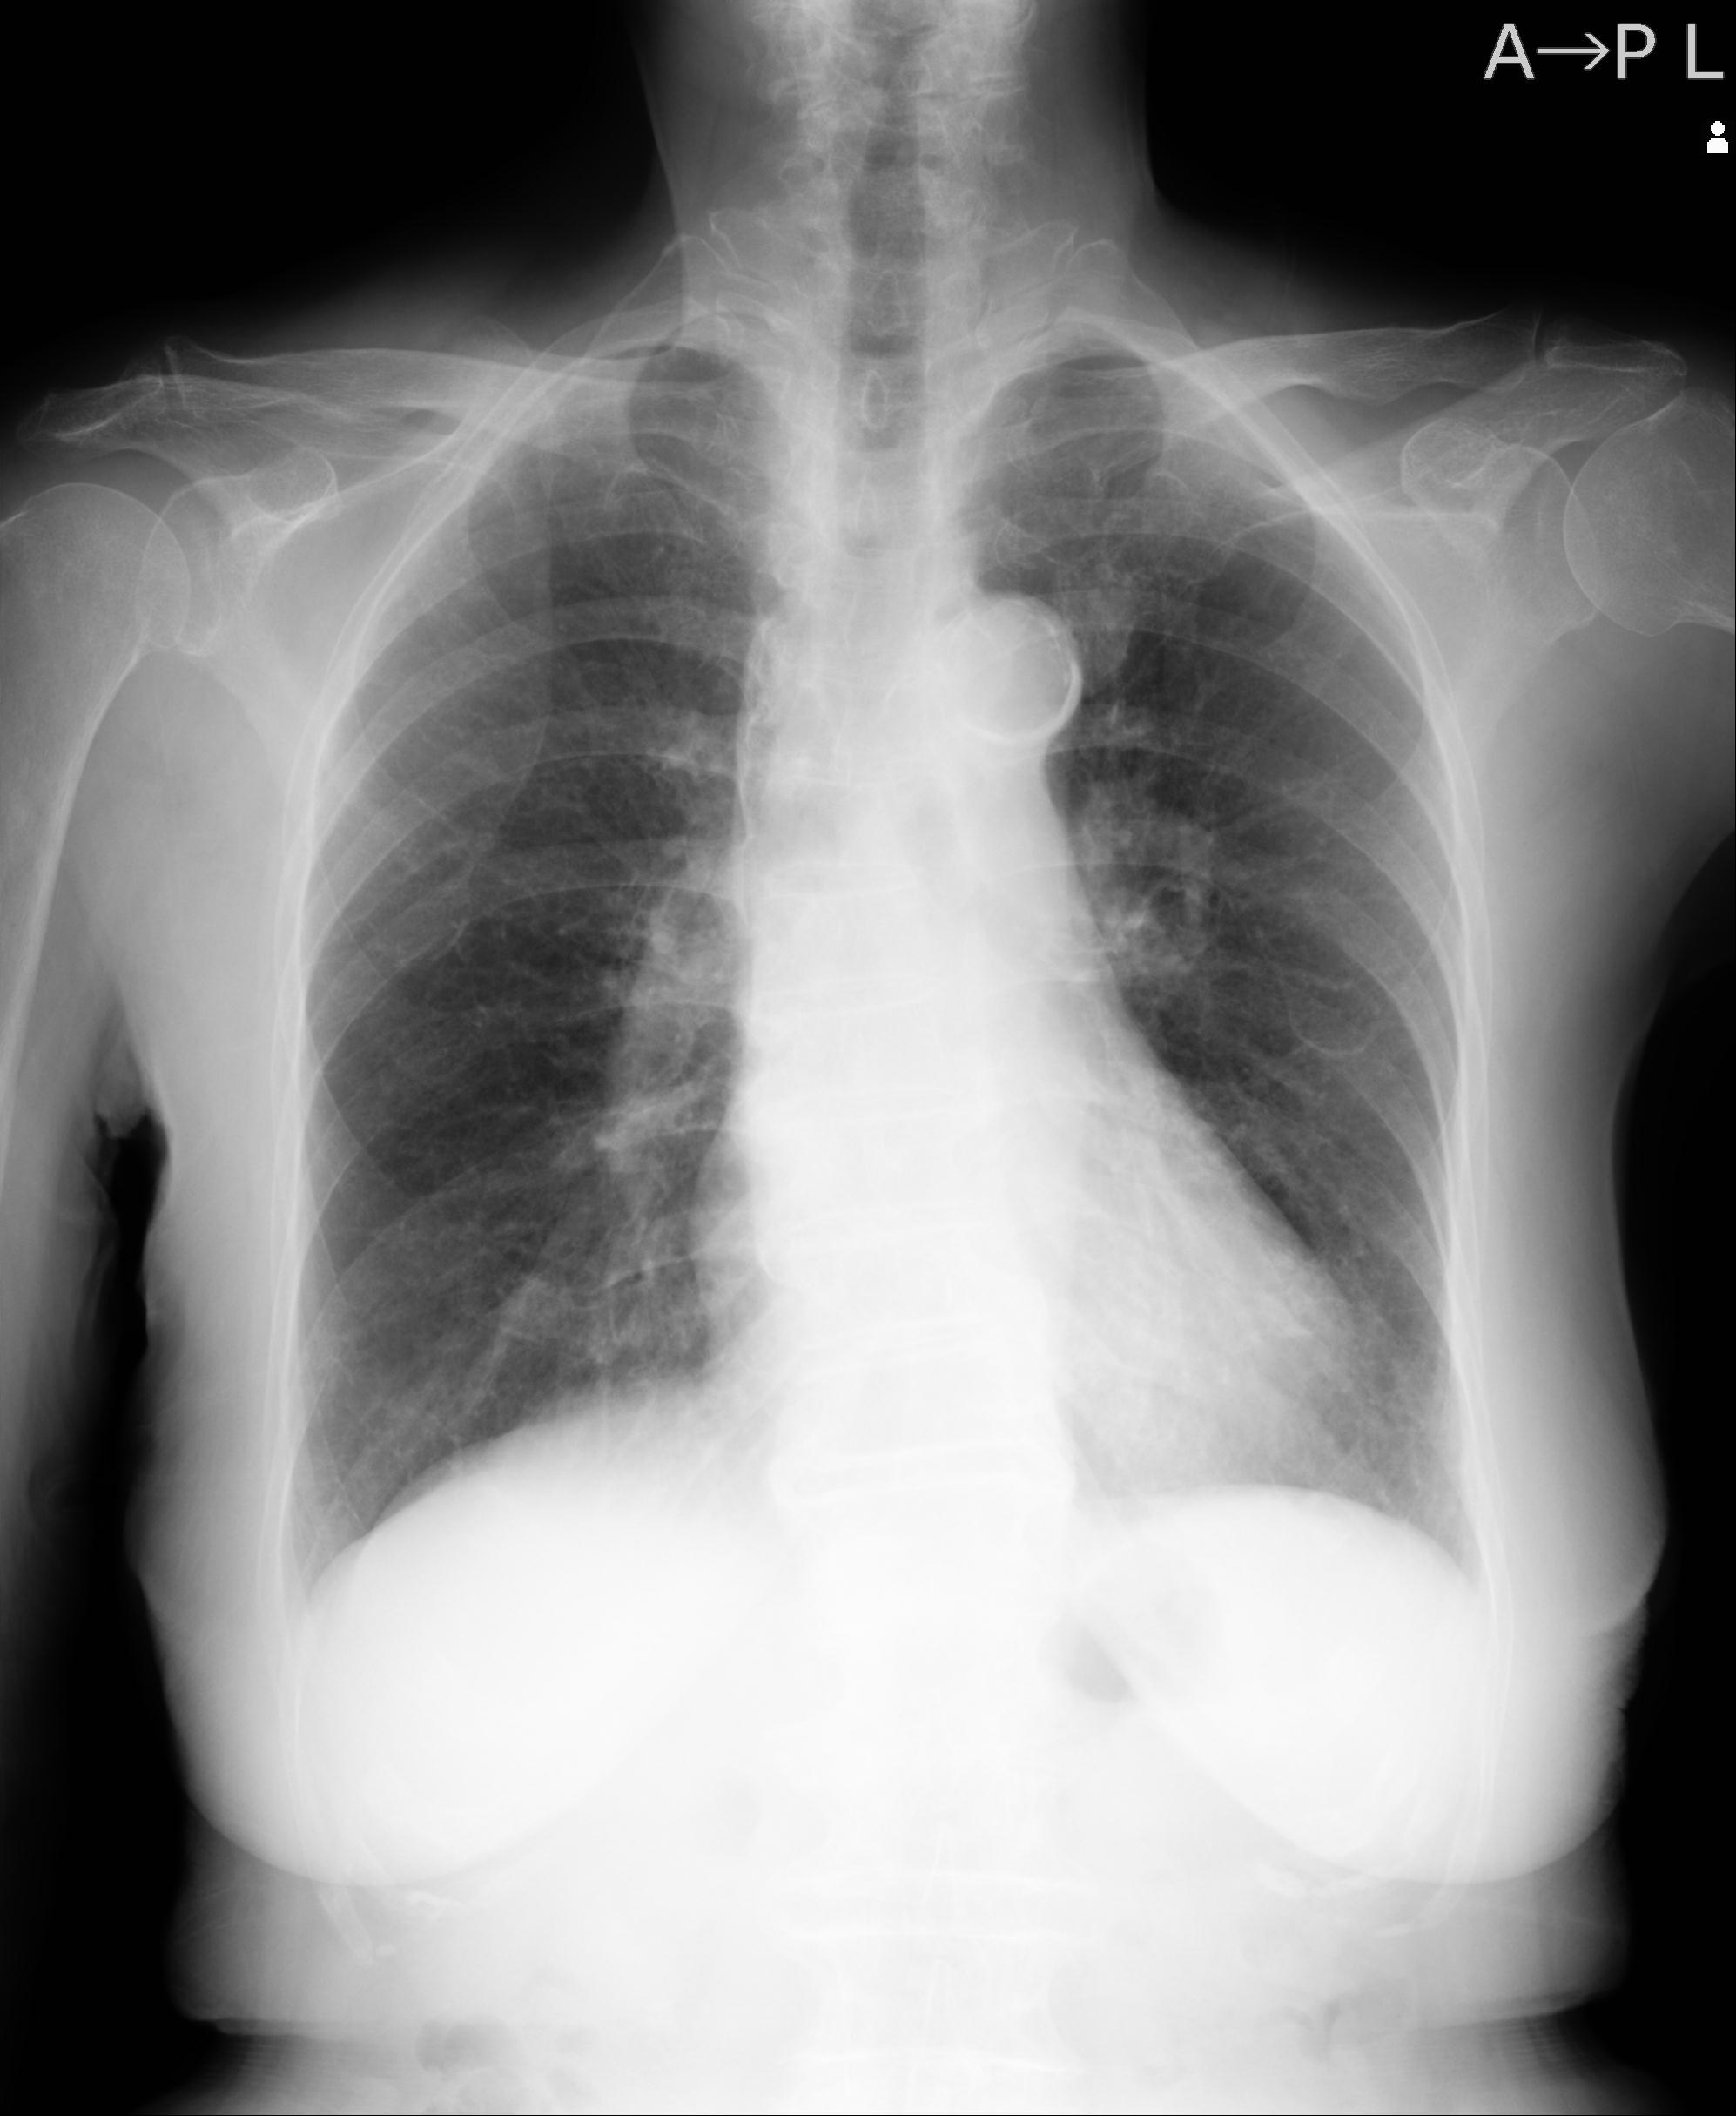

110214 12/20 肩 2R 12/21 肩 4R 72歳女性 左上腕外科頚プレート